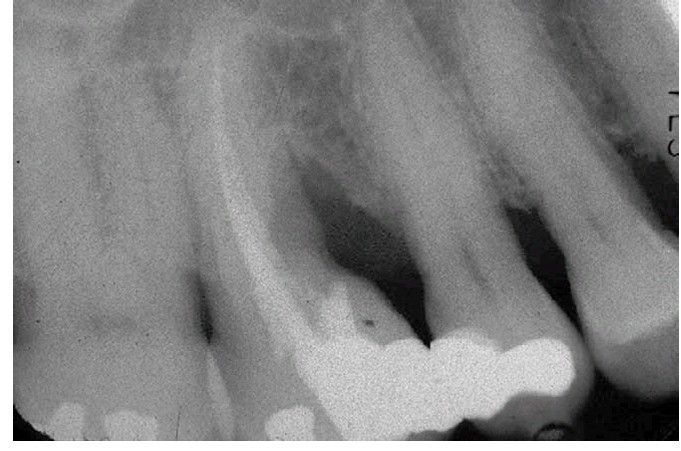

Root amputation

Periapical radiograph showing prior nonsurgical root canal treatment and mesiobuccal root amputation of tooth #3.